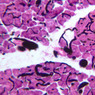

Scan slide B-36 (H&E [10x, 20x] [10x, 20x). Note that in this H&E preparation most of the pancreas consists of rather compactly arranged, darkly stained cells. The compact, darkly stained regions constitute the exocrine portion of the pancreas. (Of what organ does the exocrine pancreas remind you?) The endocrine portions of the pancreas consist of small bits, or islands, of more lightly stained tissue that is somewhat irregularly dispersed within the substance of the exocrine pancreas. Drawing on the name of their discoverer, the endocrine portions of the pancreas are known as the islets of Langerhans.

Endocrine pancreas

Although H & E staining permits ready identification of the islets of Langerhans, it does not permit differentiation of the various cell types that comprise the islets (B-36, H&E [10x, 20x, 40x-labeled]). There are no slides in the class collection that permit identification of all of the cell types of the endocrine pancreas. However, the sections on slides B-37 and B-40 permit specific identification of two cell types. Slide B-37 has been stained by the aldehyde fuchsin technique, which lends a magenta coloration to the granules of the insulin-producing B-cells. All other cells in the islets stain a dirty orange color (B-37 [10x, 20x, 40x] [10x, 20x, 40x]). Most of these orange-colored cells are the glucagon-secreting A-cells; however, you should bear in mind that somatostatin-secreting D-cells, as well as APUD cells that secrete pancreatic polypeptide are also scattered about the islet. The section on slide B-40 has been prepared by a silver impregnation method that renders some of the APUD cells in the islets (which appear as “clear cells” in ordinary preparations) dark brown or black (B-40 [10x, 20x, 40x]).